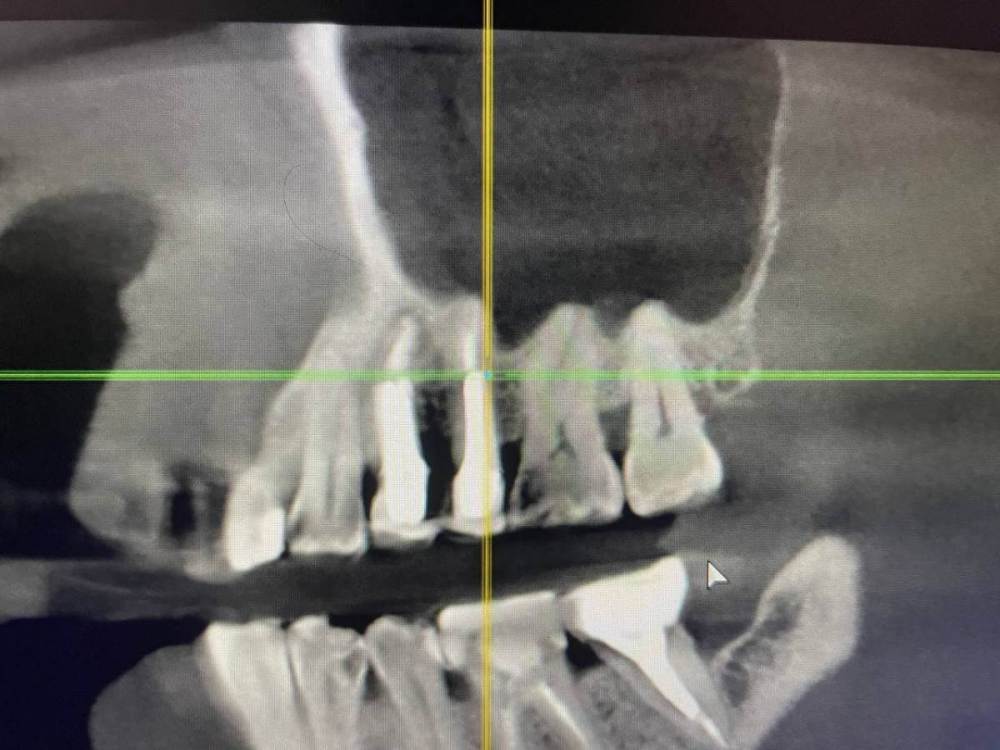

1586Doc Опубликовано 17 января, 2021 Автор Поделиться Опубликовано 17 января, 2021 еще один кейс.Утолщение слизистой гайморовой, хронический процесс на 25.26 зубахконтроль клкт через 8 месяцев Ссылка на комментарий

1586Doc Опубликовано 17 января, 2021 Автор Поделиться Опубликовано 17 января, 2021 первые 3 фото, ретрит 14 зуб4.5 фото 45 зуб. 4 Ссылка на комментарий

1586Doc Опубликовано 12 мая, 2021 Автор Поделиться Опубликовано 12 мая, 2021 ретрит зубов 15.14.26 и контроль клкт через 6 месяцев Ссылка на комментарий